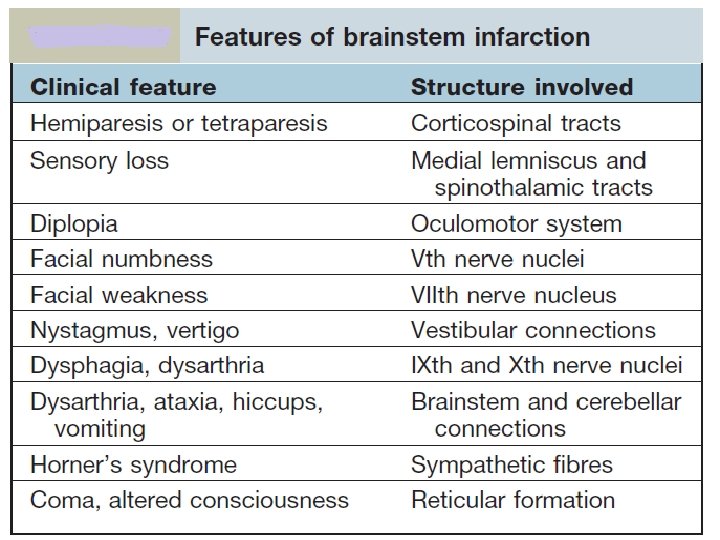

Localization of Lesion Midbrain: CROSSED HEMIPLEGIA: Ø 3 rd /4 th CN are involved on one side and hemiplegia of opposite side Pons: Ø 5 th, 6 th, 7 th and 8 th CN nuclei are present in pons. Ø One or more of these CNs are paralyzed on one side and hemiplegia is on the other side. Ø Pupils are pinpoint but reactive to light Ø Hyperpyrexia may be present Medulla Oblongata: Ø 9 th, 10 th, 11 th and 12 th CN nuclei are present in medulla. Ø One or more of these CNs are paralyzed on one side and hemiplegia is on the other side.

LATERAL MEDULLARY SYNDROME • Also called posterior inferior cerebellar artery (PICA) thrombosis and Wallenberg’s syndrome) • Acommon example of brainstem infarction presenting as acute vertigo with cerebellar and other signs. It follows • Thromboembolism in the PICA or its branches, vertebral artery thromboembolism or dissection. • Features depend on the precise structures damaged. MEDIAL MEDULLARY SYNDROME • Characterized by a set of clinical features resulting from occlusion of the anterior spinal artery. This results in the infarction of medial part of the medulla oblongata.